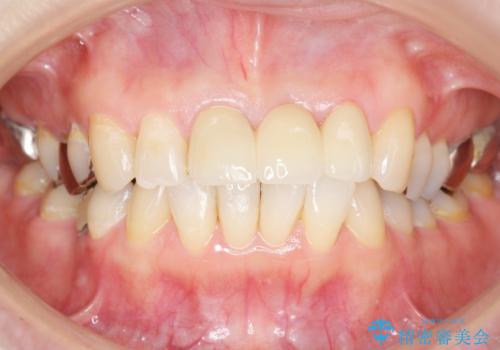

不自然なブリッジ 自然なセラミックでやりかえ 30代女性

自然な仕上がりに喜んで頂けました。

モチベーションが上がりオフィスホワイトニングもご希望され、口元の印象が明るくなりました。

クラウンの種類:オールセラミッククラウン スタンダード